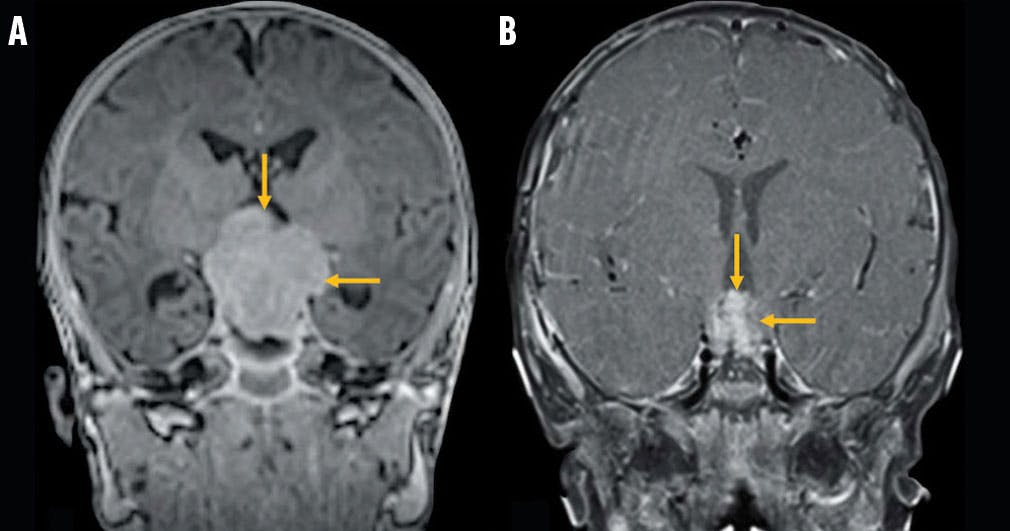

<p>Figure 2. Coronal view of a 3.5 x 3.0 x 4.1 cm solid, lobulated, noncystic, partially calcified, heterogeneously enhancing suprasellar mass (yellow arrows) was shown on T1-weighted brain MRI at presentation (A). After intravenous chemotherapy, the brain malignancy decreased in size to 1.4 x 1.8 x 1.9 cm with more heterogenous enhancement (yellow arrows; B).</p>

Figure 2. Coronal view of a 3.5 x 3.0 x 4.1 cm solid, lobulated, noncystic, partially calcified, heterogeneously enhancing suprasellar mass (yellow arrows) was shown on T1-weighted brain MRI at presentation (A). After intravenous chemotherapy, the brain malignancy decreased in size to 1.4 x 1.8 x 1.9 cm with more heterogenous enhancement (yellow arrows; B).

At the 4-month visit, the patient’s panhypopituitarism had resolved spontaneously, resulting in discontinuation of hormone treatment, excluding levothyroxine for hypothyroidism. At the 7-month visit, follow-up brain MRI revealed remarkable reduction in size of the suprasellar tumor (Figure 2B).

In the present case, the combination of high-dose chemotherapy and autologous stem cell rescue was effective. Following five treatment cycles, the suprasellar tumor shrunk to 1.4 x 1.8 x 1.9 cm in the now 14-month-old patient. Despite the low incidence of trilateral RB, and noting its serious prognostic implications, it is important to closely monitor children with bilateral and trilateral RB with MRI.